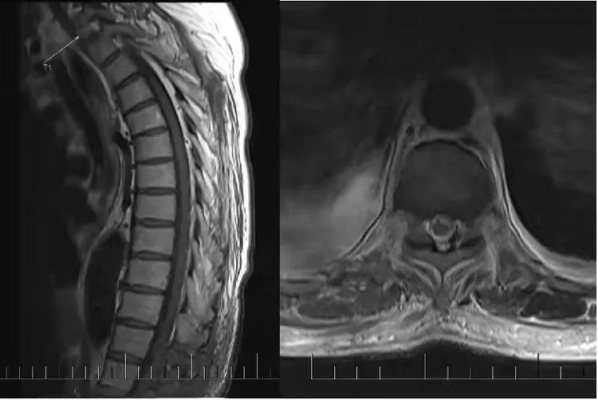

王大姐,今年41岁,因四肢麻木、无力两月余,并加重7天来我科就诊。通过查体发现王大姐双上肢腱反射消失,双下肢腱反射活跃,双上肢体肌力5-级,右下肢肌力4+级,左下肢肌力5-级,双侧Babinski征阳性,侧肘关节以下痛触觉减退,双侧膝关节以下(腓侧重于胫侧)痛触觉减退,深感觉粗侧正常。(可疑T4平面以下痛触觉减退),双侧指鼻试验、跟膝胫试验阳性,宽基底步态,闭目难立征检查不配合,脑膜刺激征(-);当天复查颈椎平扫MR结果示::颈1-胸2椎体层面脊髓占位性病变,考虑室管膜瘤可能。肌电图的结果:EMG:被检部分肌见纤颤正尖波,轻收缩个别被检肌见MUP 偏宽大,重收缩偏弱。NCV: 被检运动和感觉神经传导速度和波幅正常范围。运动神经F波潜伏期正常范围、双侧胫神经 H反射正常范围。提示:神经源性损害肌电改变,累及右侧C5-T1和左侧C5-C7支配肌,脊髓前角细胞或根性损害。为避免肿瘤进展影响后期的生活质量,王大姐 及家属非常信任欧阳一彬主任团队为王大姐进行手术。手术方式:全麻下行高位颈髓多节段髓内肿瘤切除+椎管重建手术。手术过程顺利,达到良好的治疗预期。